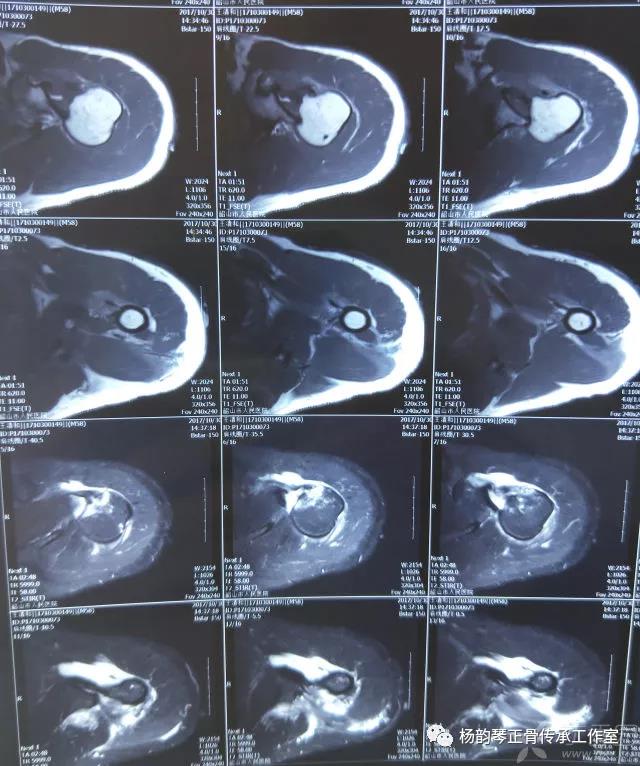

简要病史:骑摩托车跌倒致左肩部肿痛,活动受限,就诊于当地医院,拍片及磁共振检查后诊断为肩袖损伤及肩关节半脱位,予以悬吊固定,因症状缓解不明显就诊于我院。外院拍片情况如下:

应该说是一个典型的“灯泡征”影像,但是并未引起注意。

磁共振检查也完善了,还是报了个肩关节半脱位……影像科已经把坑挖好了……